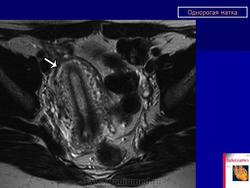

МПС. Женская репродуктивная система. Аномалии и варианты развития. Матка. Однорогая матка. +

Аномалии и варианты развития. Однорогая матка.